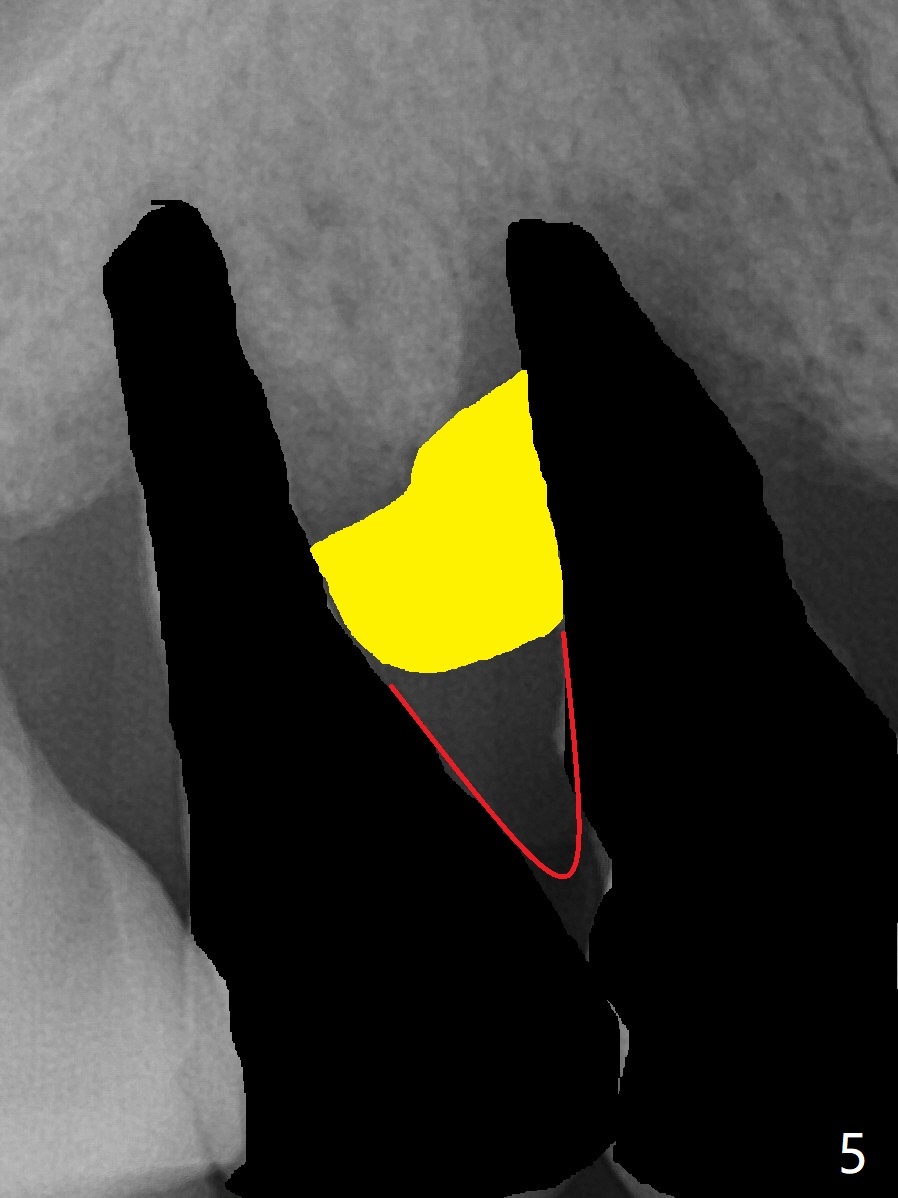

图三红线代表龈乳头,当两个邻牙拔除后,没有特殊处理,龈乳头不可避免收缩(图四)。如何预防呢?拔除4时,发现牙槽窝肉芽组织延申到牙槽嵴与乳头之间(图五:黄色)。刮治肉芽组织后,在空缺处,填入粘性骨粉(图六:圆圈),应该能够减少术后龈乳头萎缩。